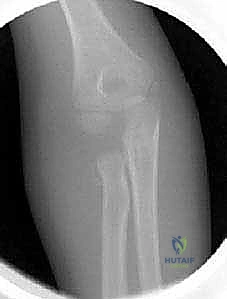

2. التصوير الشعاعي (X-Rays)

هو الخطوة الأساسية لتأكيد الكسر. يتم التقاط صور من زوايا متعددة (أمامية خلفية، وجانبية، ومائلة).

* علامة وسادة الدهون (Fat Pad Sign / Sail Sign): في بعض الأحيان، خاصة في كسور النوع الأول غير المزاحة، قد لا يظهر خط الكسر بوضوح في الأشعة. في هذه الحالة، يبحث الدكتور هطيف عن "علامة الشراع" أو ارتفاع وسادة الدهون المحيطة بالمرفق في الصورة الجانبية، والتي تدل على وجود نزيف مفصلي (Hemarthrosis) يؤكد وجود كسر خفي.